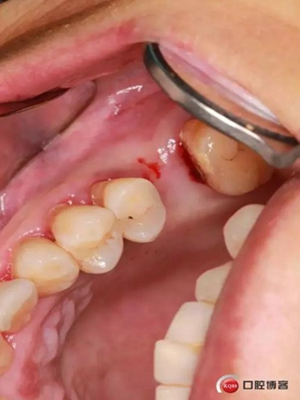

六個(gè)月之后